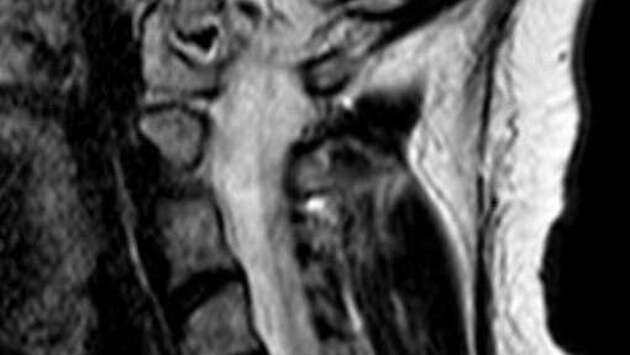

Врачи Истринской больницы спасли от паралича руки 37-летнюю женщину, у которой в шейном отделе нашли грыжу. Об этом сообщили в пресс-службе минздрава Московской области. Пациентка обратилась с жлобами на изматывающую боль в руке. Ей провели МРТ, которое показало, что в шейном отделе сформировалась грыжа размером 8 мм. По словам медиков, образование сдавливало спинномозговой канал и корешковое отверстие, угрожая двигательной функции. "Мы провели сложнейшее микрохирургическое вмешательство, в ходе которого удалили грыжу и стабилизировали позвоночник с помощью современного импланта", - рассказал нейрохирург Николай Карпов, отметив, что операция длилась два часа 20 минут. На пятые сутки женщину выписали на амбулаторное лечение. Она идет на поправку.